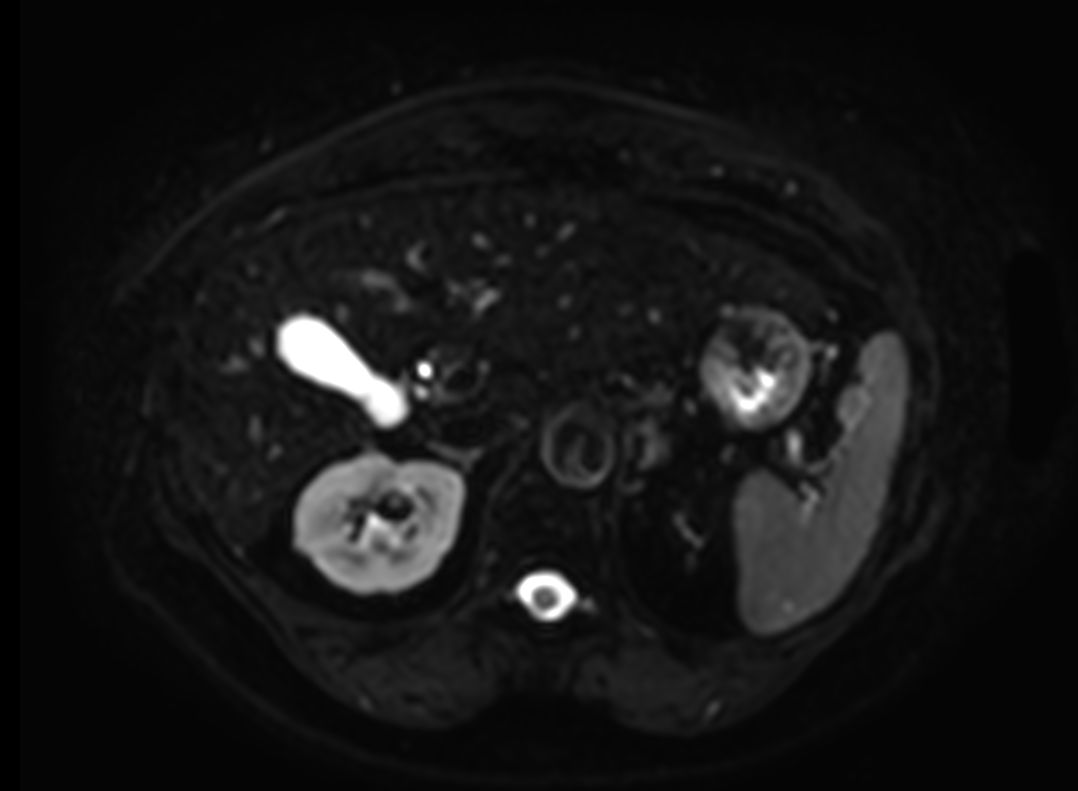

Diffusion (b0)

Diffusion (b1000)

Diffusion (ADC)